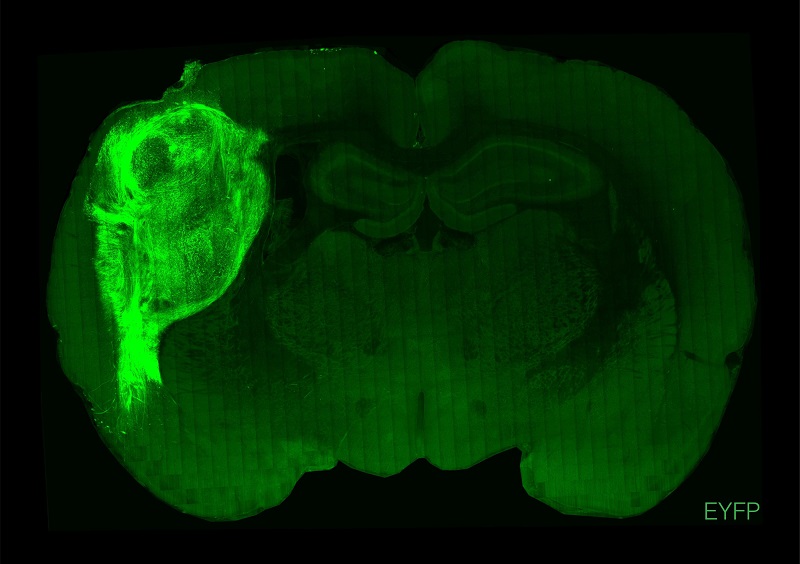

用熒光蛋白標(biāo)記的人類類腦在大鼠的大腦中。

圖片來源:斯坦福大學(xué)